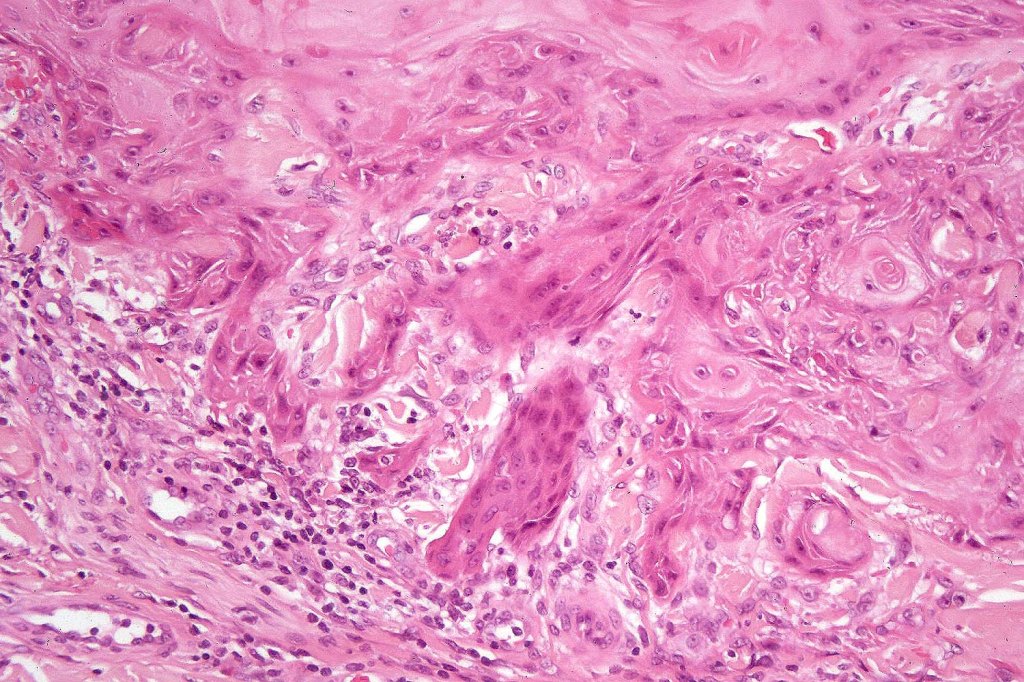

•Well differentiated squamous epithelium often with a characteristic ground-glass appearance

•Only mild pleomorphism & basally located mitoses

•With evolution, the epithelium flattens with underlying fibrosis and chronic inflammation including a foreign body giant cell reaction to keratin

. Exceptionally, perineural infiltration and vascular involvement has been documented. If present, this should be viewed with concern as risk of recurrence or metastatic spread is significant

Below is a fascinating case shared on McKee Derm by Dr. James Simpson. There is an obvious keratoacanthoma but at the edge of the lesion there is marked atypia with nuclear enlargement and pleomorphism. This is also evident in the adjacent epidermis and in the deeper nests.